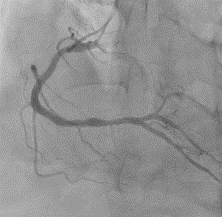

冠動脈造影検査(CAG)

心臓を栄養する冠動脈の状態を調べます。

冠動脈は胸部の大動脈から左右に別々に出ており、それぞれにカテーテルを入れて検査をします。

左冠動脈造影

右冠動脈造影

経皮的冠動脈治療(PCI)

冠動脈検査などによって発見された狭窄部位を拡張させる治療です。

ステントと呼ばれる金属製の筒を留置します。